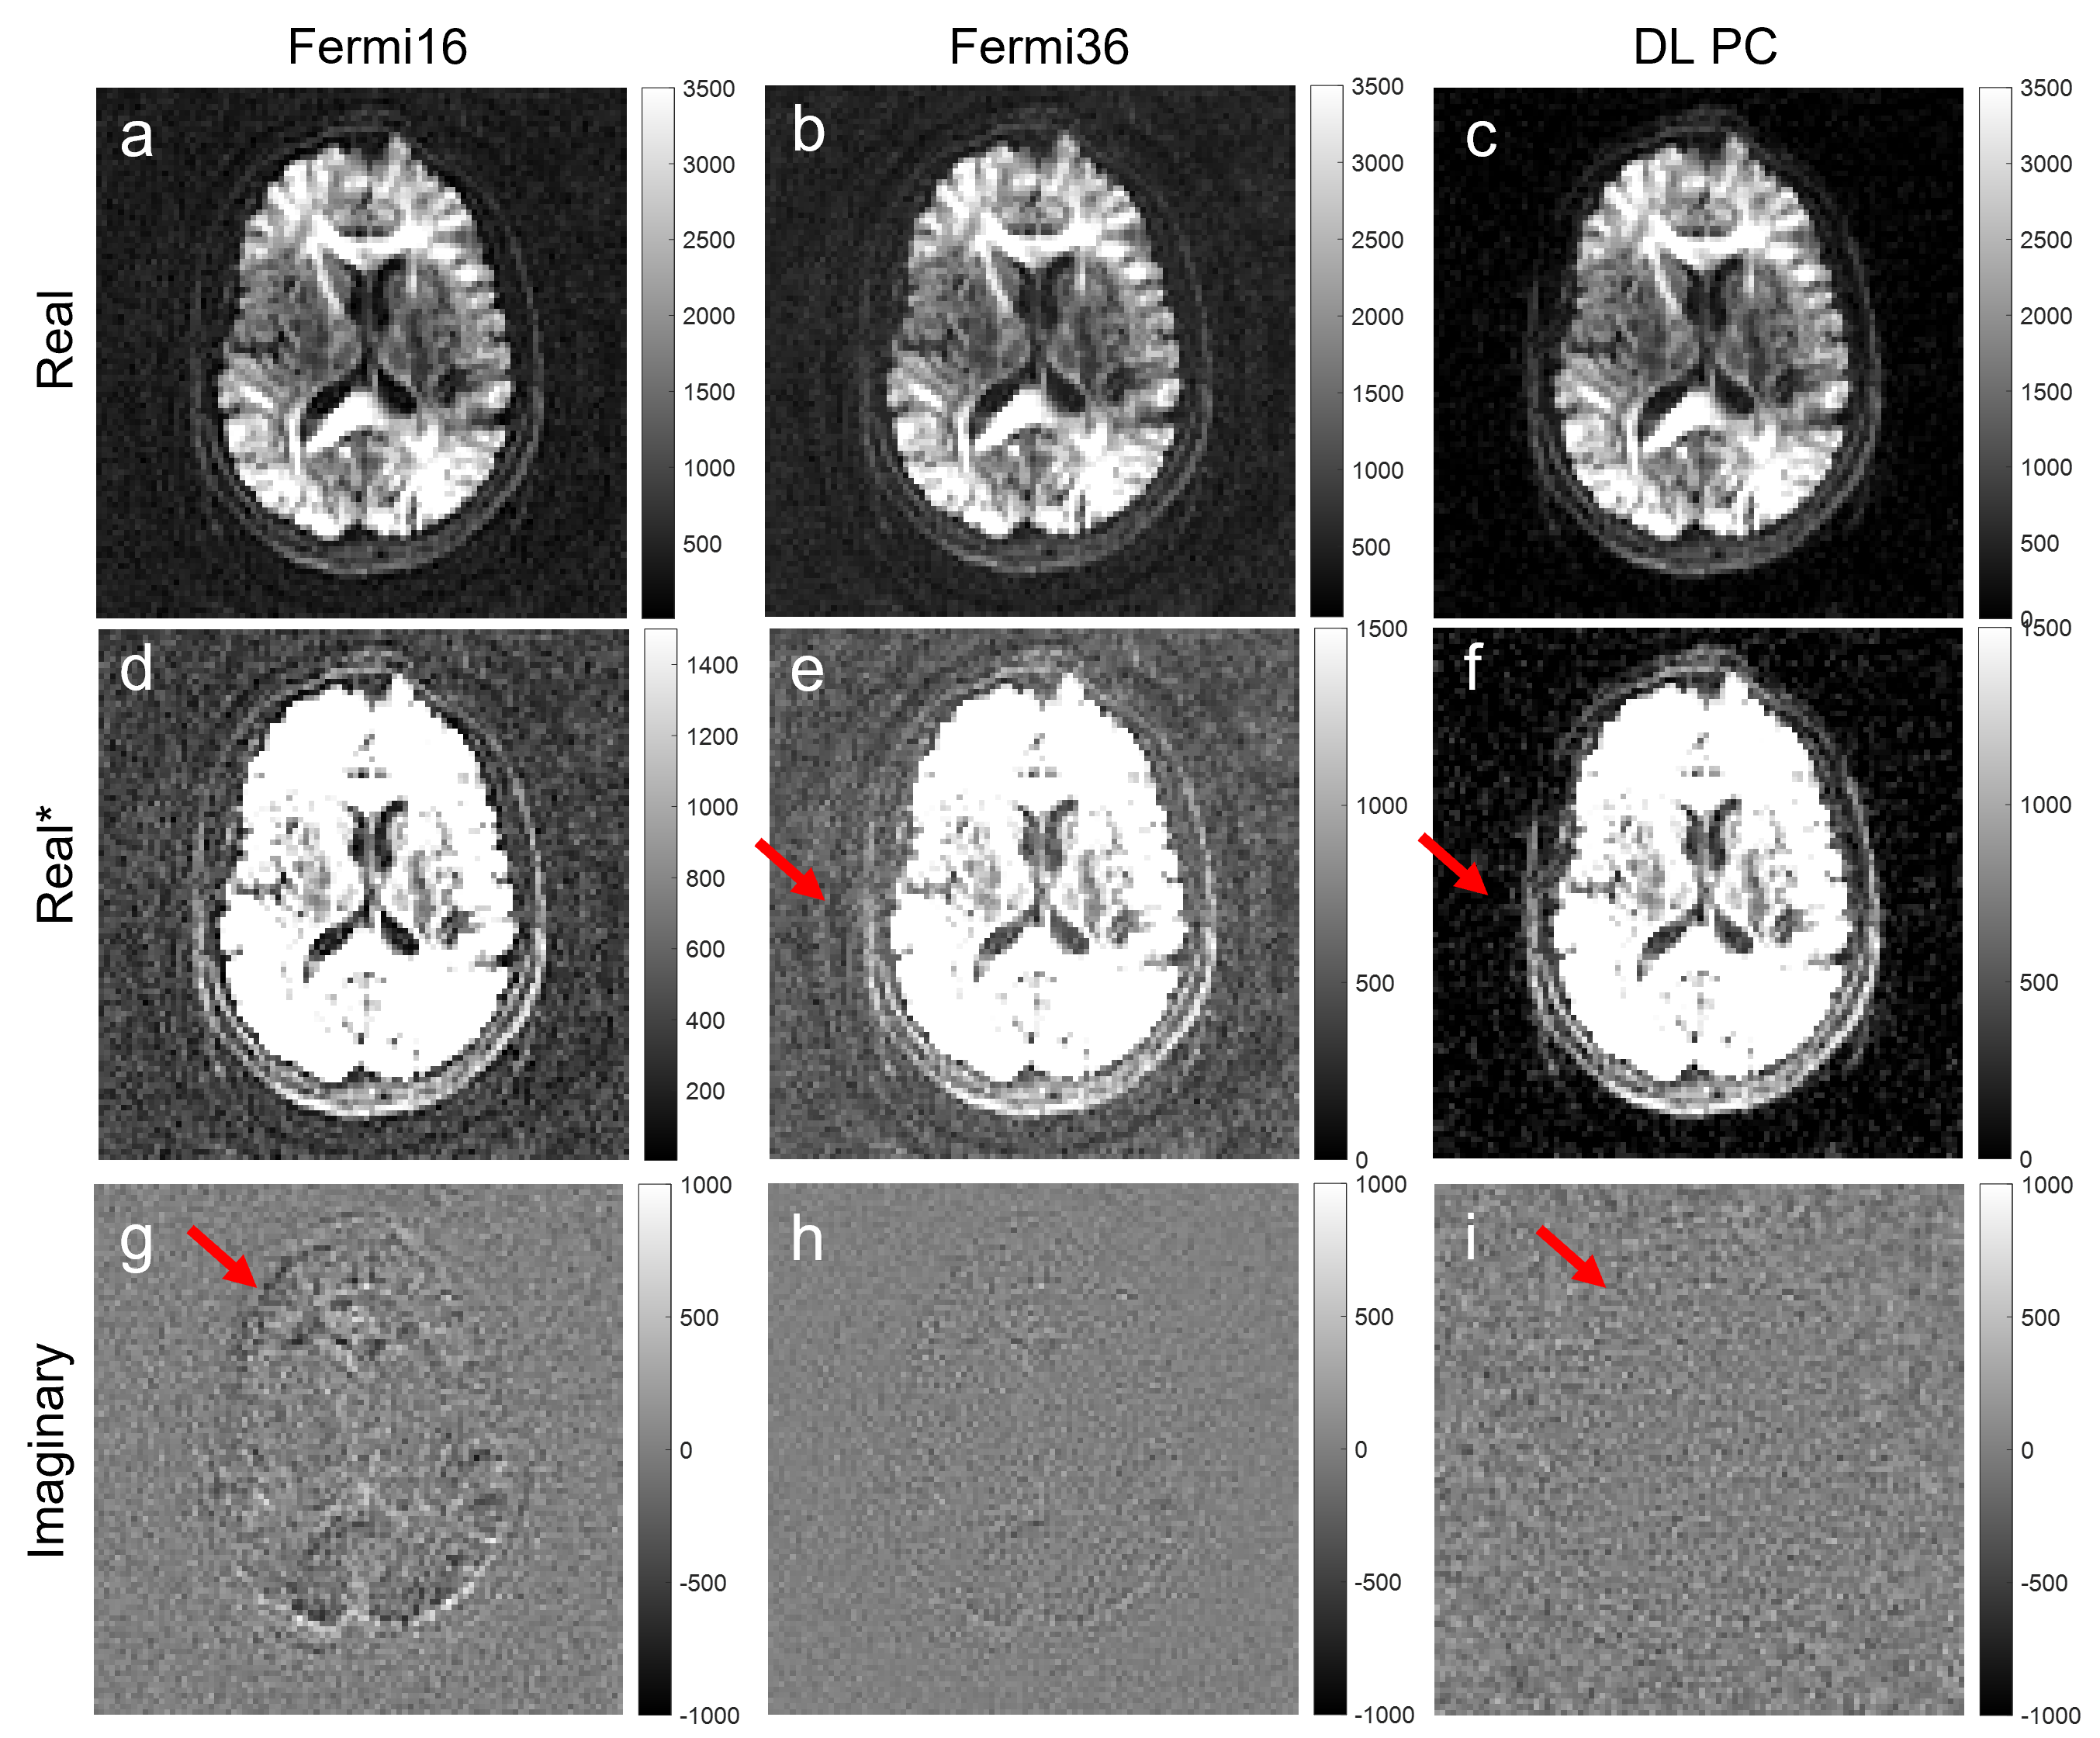

Figure 2 shows the brain DW images at b=2500. Phase correction with a large kernel (Fermi16) minimized the signal bias and reduced background noise in the averaged image, but left more signal in the imaginary channel (Figure 2g). Reducing the kernel size (Fermi36) reduced the signal in the imaginary channel but resulted in increased signal bias and higher noise floor (Figure 2e). DL-based phase correction achieved minimal signal bias and noise floor while preserving signal in the real channel (Figure 2f, 2i).

Figure 2. Complex averaging using filter-based phase correction and DL-based phase correction with b=2500 brain images. (a-c) are the real images; (d-f) are the same images but with a different window level to show the background noise; (g-i) are the imaginary images. Compared to a small kernel (Fermi36), a large kernel (Fermi16) could reduce the signal bias, resulting in a lower noise floor (d vs e). However, more signal was also left in the imaginary channel (g vs h). In contrast, DL-based phase correction showed lowest noise floor and minimum loss of signals.